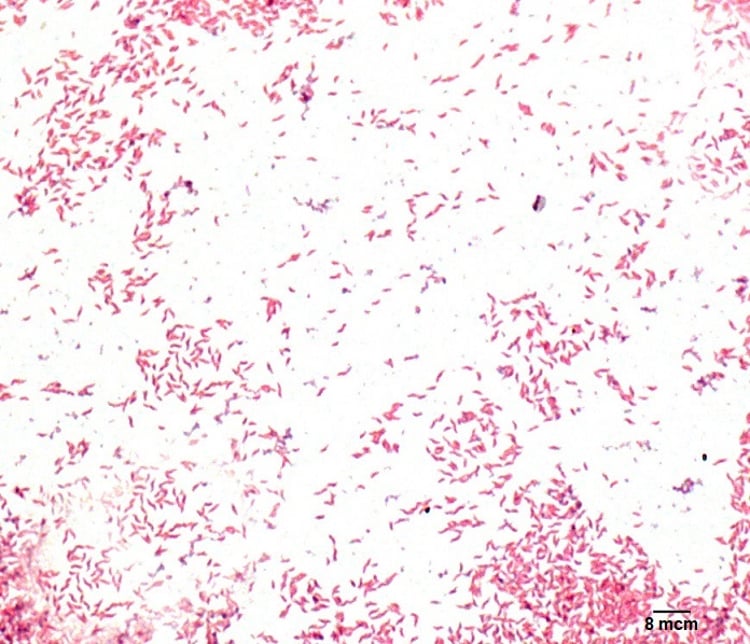

Campylobacter spp.

Campylobacter es en realidad un grupo de bacterias de configuración espiral que pueden causar enfermedad en los seres humanos y los animales. La mayor parte de la enfermedad en los seres humanos es ocasionada por la especie Campylobacter jejuni, pero 1 % de los casos humanos de Campylobacter son ocasionados por otras especies.[2][3]